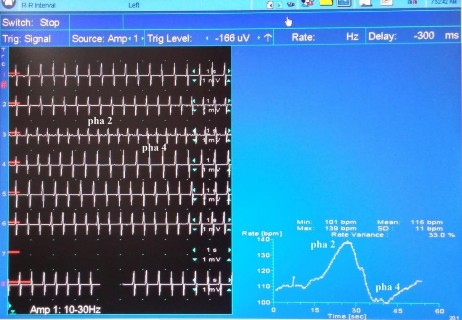

Hình 2.6 Biến thiên nhịp tim bình thường với test Valsalva (Chỉ số Valsalva = 1,4)

(Nguồn: bệnh nhân Diệp H, năm sinh 1966, thực hiện test tại phòng điện cơ, bệnh viện Chuyên Khoa Ngoại Thần Kinh Quốc Tế)

Tỷ số Valsalva = nhịp tim nhanh nhất của pha 2/ nhịp tim chậm nhất của pha 4 (khoảng cách R-R dài nhất của pha 4/ khoảng R-R ngắn nhất của pha 2)

Cho bệnh nhân hít sâu vào và thổi mạnh vào một cái ống có lực cản (nối với máy đo huyết áp), sao cho tạo được và duy trì áp lực 40mmHg trong 15 giây. Sau đó, cho bệnh nhân nghỉ 3 phút là lặp lại nghiệm pháp này thêm 2 lần nữa. Chọn tỷ số Valsalva cao nhất trong 3 lần làm kết quả cuối cùng.